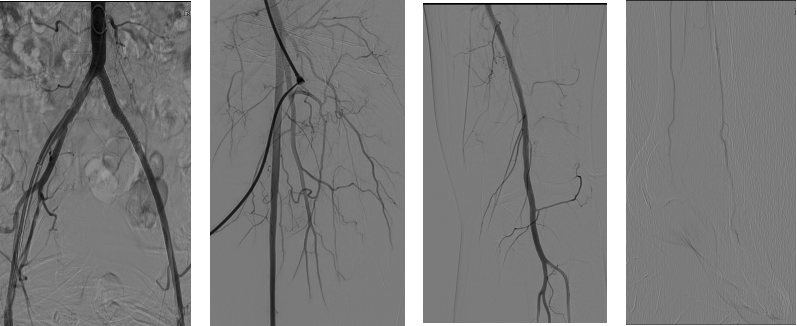

术后造影结果

术后造影显示,支架呈现8mm-7mm-6mm的梯度锥形,管腔打开完全,定位精准,贴壁良好。

术后造影